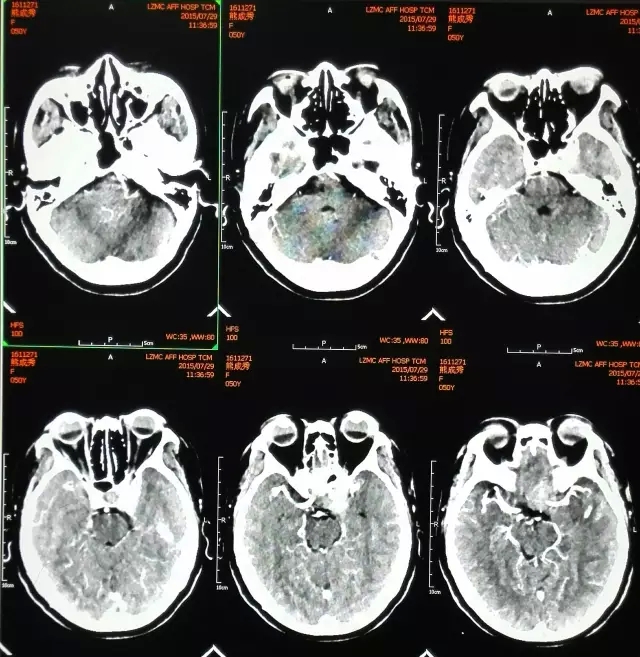

术前CT片

家住宜宾市珙县的熊某,女,51岁,左眼视力下降3年,两年前因头痛加重到医院检查,被诊断为左侧海绵窦肿瘤。患者及家属辗转多家医院均因肿瘤位置深、手术风险高而被婉拒手术,后慕名到四川医科大学附属第二医院神经外科就诊。

入院后,四川医科大学附属第二医院大外科副主任、神经外科主任顾应江为患者进行了详细的检查,经与患者及家属充分沟通,于8月6日在气管插管全麻下为患者实施左侧海绵窦肿瘤显微切除术,术后病理检查诊断为“脑膜瘤(沙粒体型)”。

“术中发现患者肿瘤位于左侧鞍旁,包绕左侧视神经、颈内动脉等重要结构,手术难度非常大,危险系数也很高,稍有不慎患者很可能会出现视力受损、眼球活动障碍、内分泌紊乱等并发症,甚至危及生命。这次手术很顺利,患者昨天(8月16日)康复出院了。”顾应江主任说道。